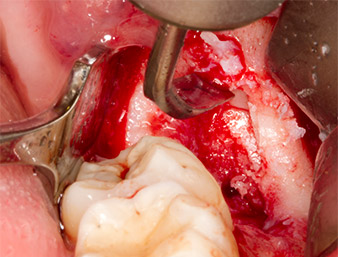

Pour obtenir un matériau autogène en vue du traitement ultérieur de la plaie, des fragments osseux sains sont collectés autour du reste radiculaire à l'aide d’un insert piézochirurgical (Piezomed B5) (Fig. 5).

Pour exposer le reste radiculaire en minimisant le traumatisme causé aux tissus, un autre insert est utilisé (Piezomed S2) qui est principalement indiqué pour la préparation de la fenêtre latérale dans les élévations de plancher sinusien. La boule diamantée est également utilisée pour adoucir les bords osseux tranchants (Fig. 6 et 7). Tous les inserts Piezomed sont utilisés avec le paramétrage par défaut automatique, et sans la fonction Booster.